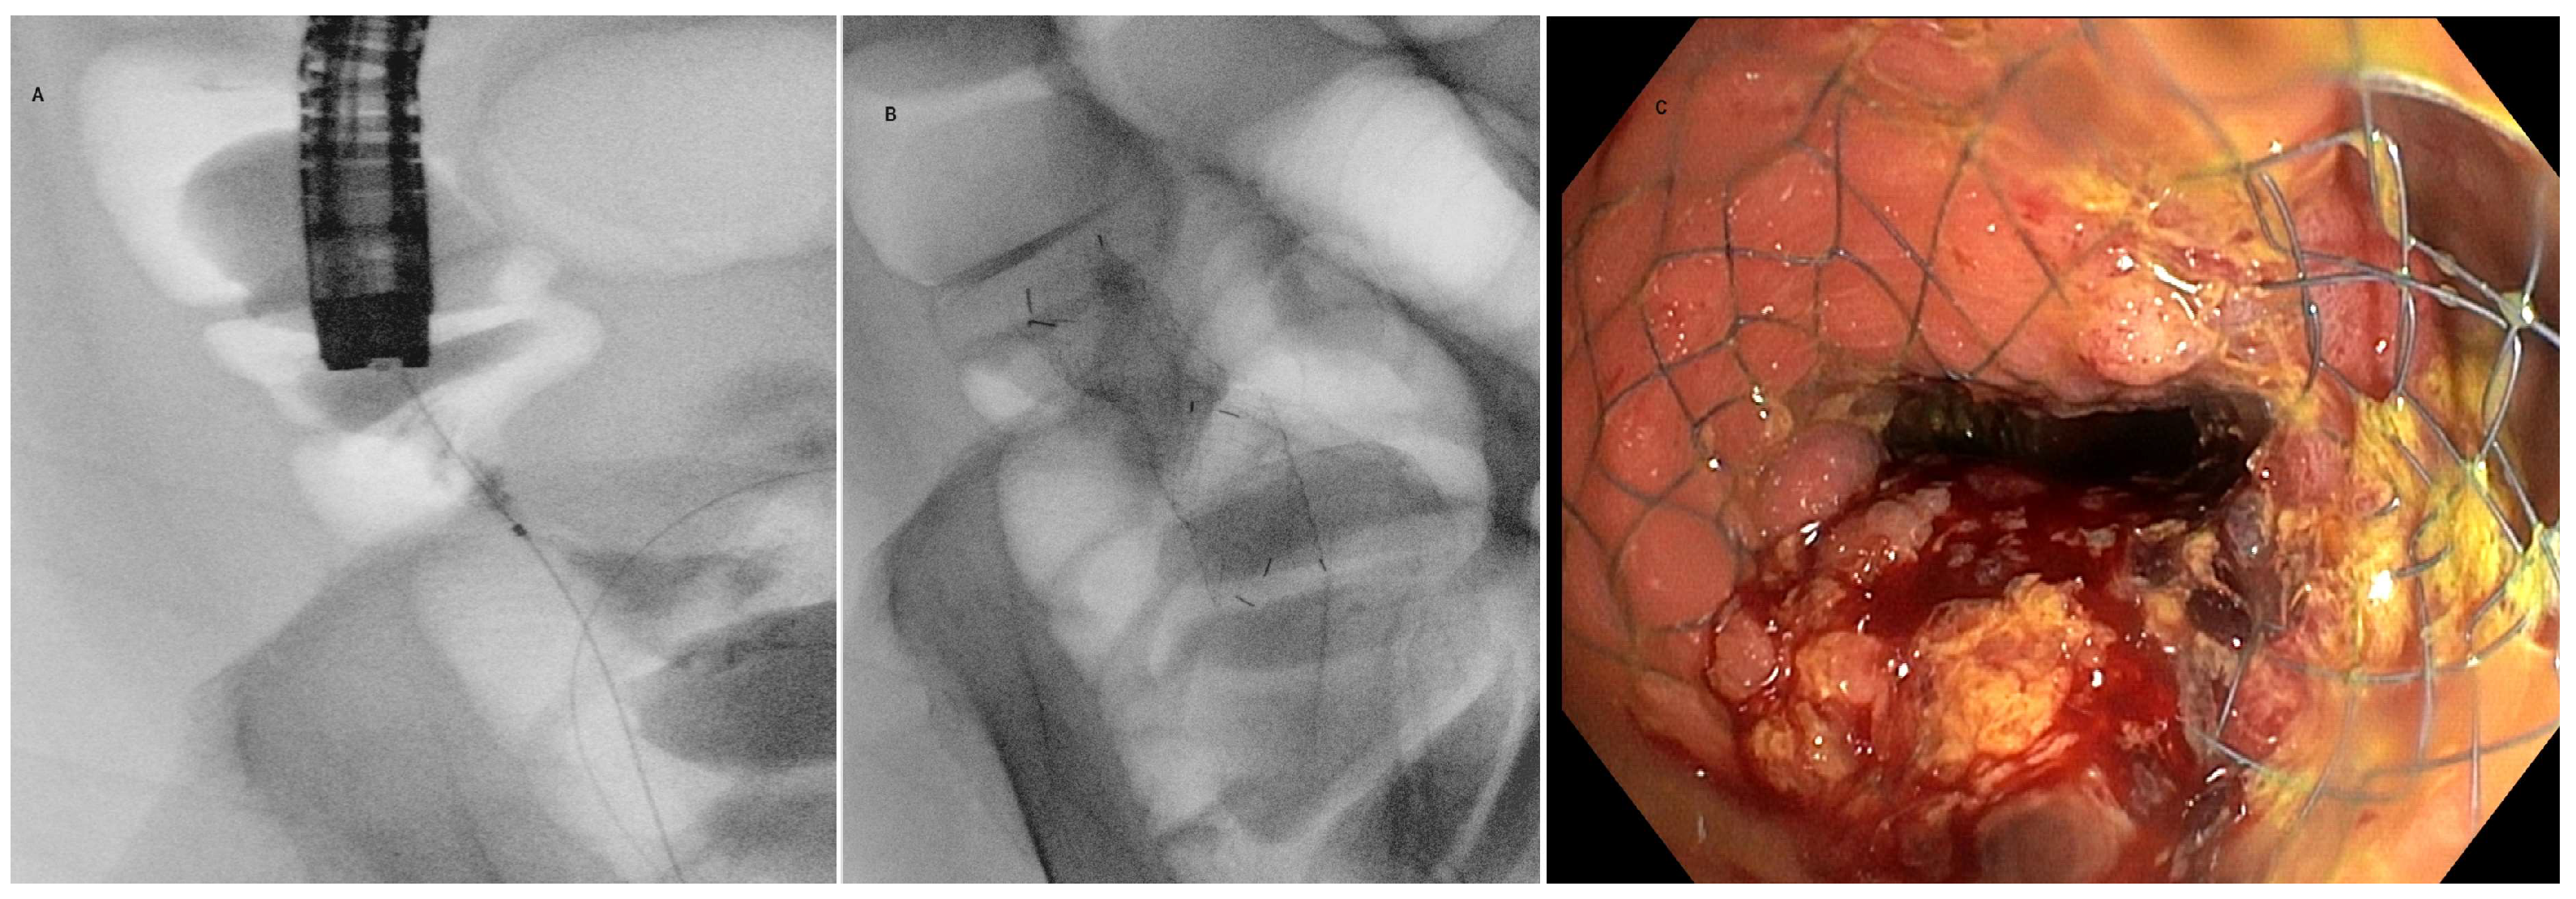

5.2. Technique